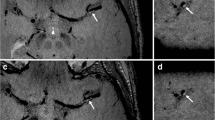

Cross-sectional imaging was performed using a 3 T MR scanner (HDx, GE Healthcare, USA) and an 8-channel phased array brain coil. 3D time-of-flight (TOF) magnetic resonance angiography (MRA) was performed for positioning. Based on the use of MRA, the scan plane was angled to ensure that the cross-sectional images were perpendicular to the diseased section (Fig. 1). Black blood 2D fast spin-echo (FSE) T2-weighted (T2), T1-weighted (T1) and gadolinium-enhanced T1-weighted (CE-T1) images of 12 sections were acquired consecutively. A detailed description can be found in the Supplemental Materials.

MRI images showing an MCA atherosclerotic plaque in a symptomatic patient. A mixture of fresh and chronic infarction involving the right periventricular and frontal subcortical regions was seen in DWI (red dashed curve); the plaque is shown by an arrow in the TOF image, and a cross section at MLA is shown in T2, T1 and CE-T1 images (white arrows: plaque and red asterisks: lumen)

Degree of luminal stenosis was computed from TOF maximum intensity projection (MIP) images following WASID criterion [18]. A plaque was identified if plaque burden [PB = (total wall area - lumen area) / total wall area × 100 %] > 40 %. Lesions with luminal occlusion were identified by using both TOF and T2-weighted images. Lumen and outer wall boundaries were manually segmented in each MR image in which plaque was present using CMRTools (CVIS, UK) (Fig. 2). Minimal luminal area (MLA), PB, plaque volume (PV) and plaque length (PL) were computed based on the segmentation. For those with luminal occlusion, stenosis was 100 %, MLA 0 mm2 and PB 100 %. MR signal intensity may vary within individuals due to factors such as coil positioning. Normalized signal intensity to adjacent grey matter in T1, T2 and CE-T1 images were therefore used for analyses (Fig. 2).